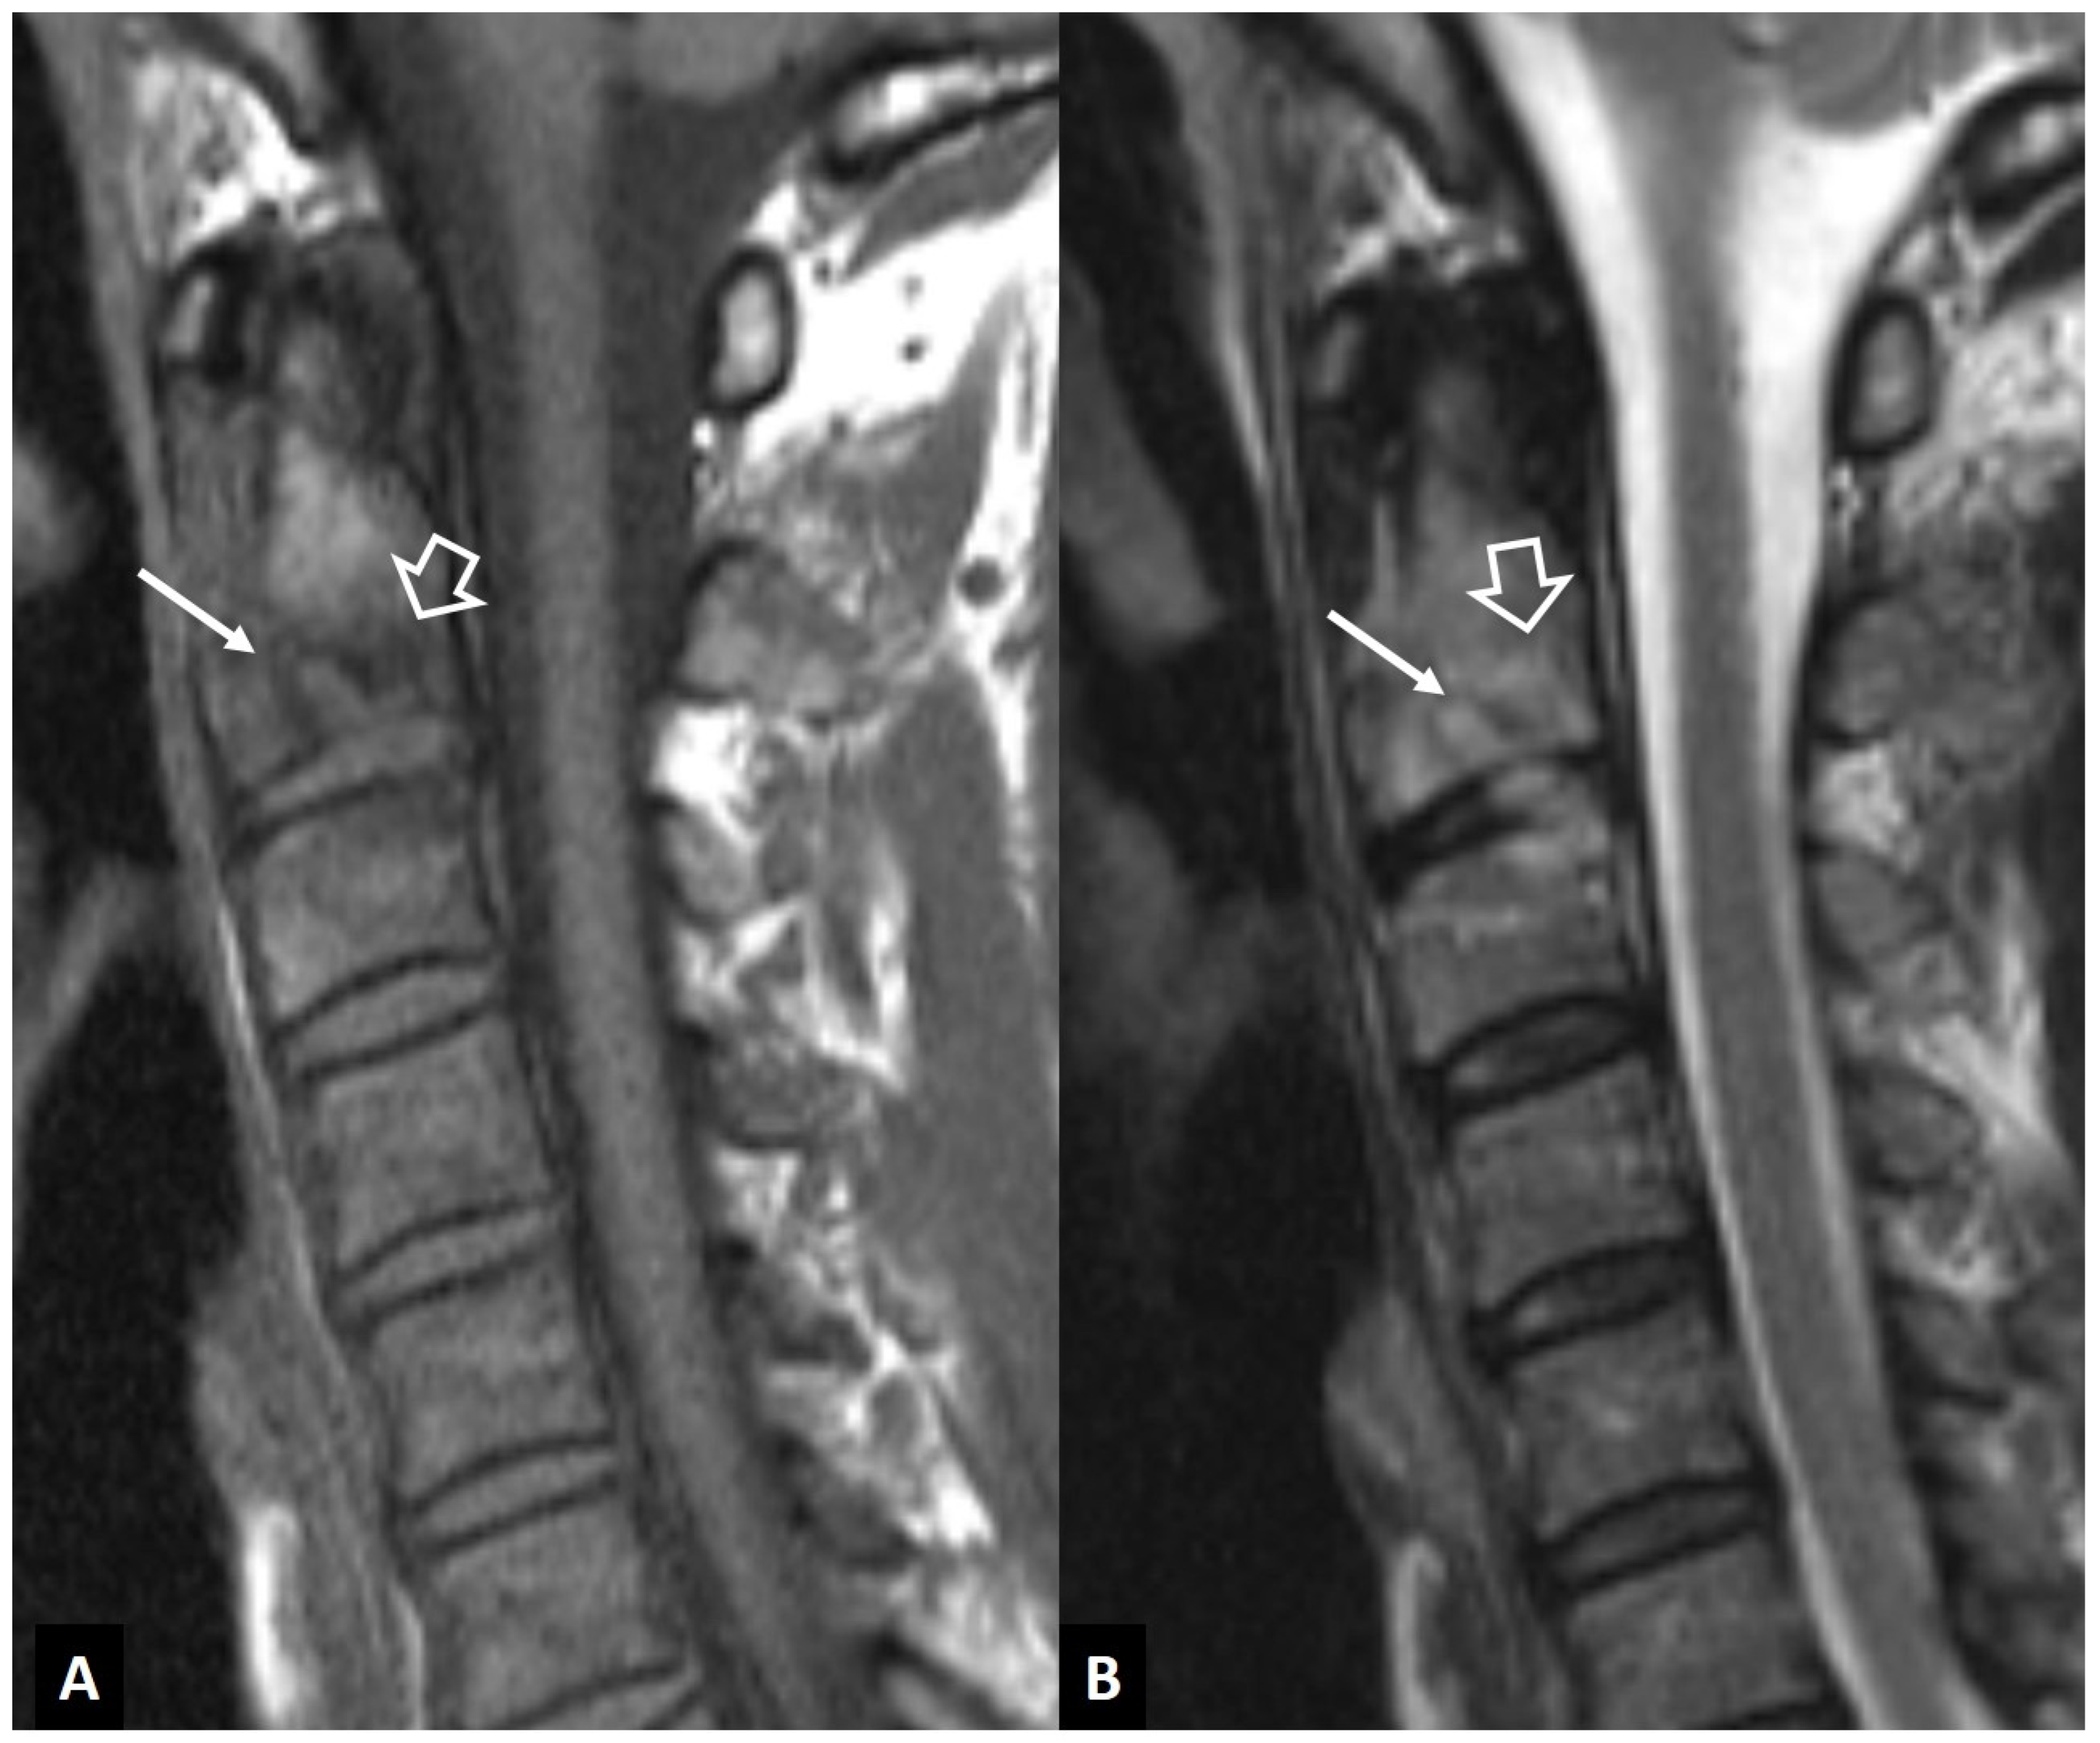

2.1.4. Destructive Spondyloarthropathy

2.1.8. Rheumatoid Arthritis